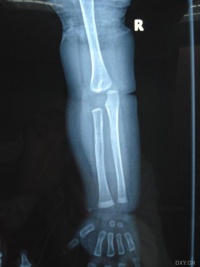

外伤性骨化性肌炎也称局限性骨化性肌炎,只显单一病灶。多见于30岁以前。常发生在外伤后,也有少数病例为并发与其他疾病者,例如发生在偏瘫、脊髓前角灰白质炎

,烧伤或破伤风病人。外伤后,软组织内出血可能是造成骨化的原因。常于外伤2-3周后,在软组织出现钙化及骨化。病变常出现在易接受外伤的部位,如肘、股、臀部。在邻近长骨的骨干部分沿骨干的方向排列,呈层状骨化,而且于一处或数处可与邻近骨相联。病变很少伸延到骨端及关节的部位。

x线特征:受伤后不久可出现局限性肿快。伤后3-4周,在肿快内显示毛状致密象,其临近骨将显示骨膜反应。伤后6-8周,病变边缘部清楚地被致密骨质所包绕,而具有新生骨的外貌。软组织肿块的核心部有时显囊性变且逐渐扩大其内腔,到晚期而显出类似蛋壳状的囊肿。伤后5-6个月肿块收缩,因而肿块与邻近的骨皮质和骨膜反应之间显出x线透亮带。